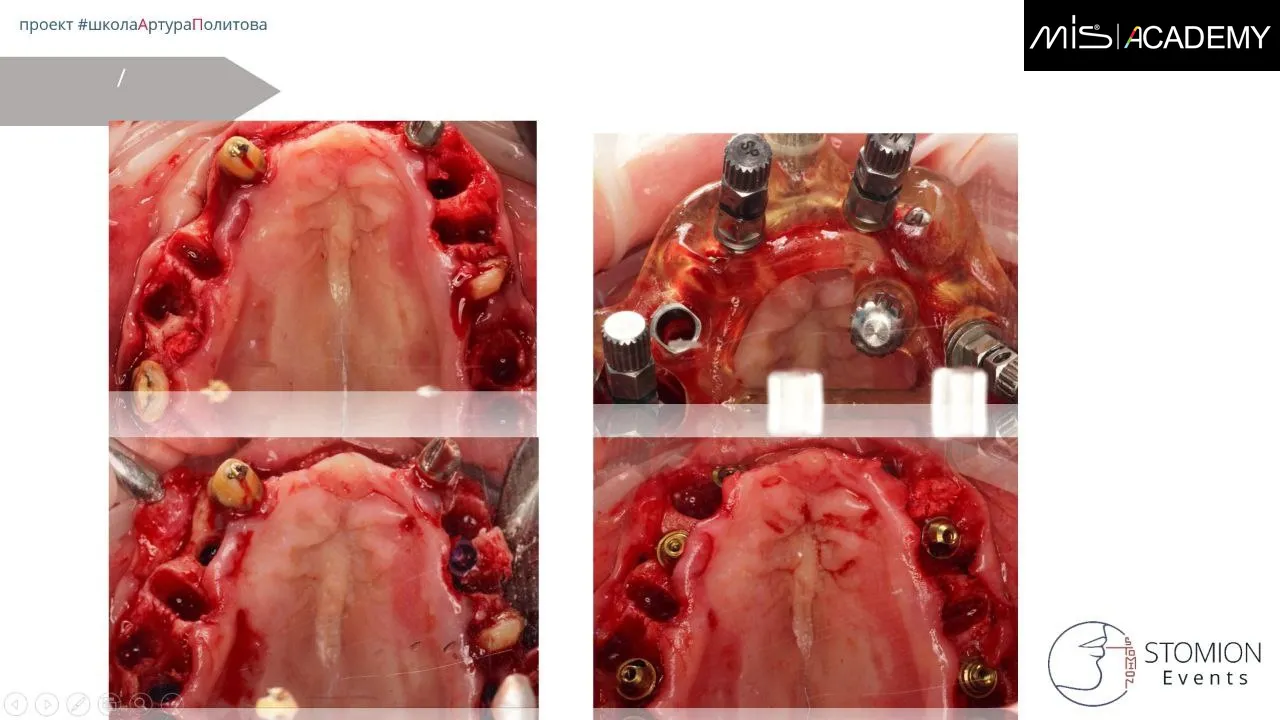

В продолжение предыдущего случая, верхняя челюсть. Удаление не состоятельных и за компанию парочку состоятельных зубов.

— Оставили 4 зуба для опоры НХШ.

— Отслойка полнослойного вестибулярного лоскута, позиционирование на зубы НХШ, вестибулярно — накостная фиксация, небно — пины для стабилизации шаблона трансмукозно.

— Установка имплантатов MiS C1 в позициях 6-4-2-1-4-6.

— Проведена контурная пластика методом «Морковки» Кури.

— Лунки зубов заполнены Bio-Oss S, всё перекрыто А-PRF.

— Установлены ФДМ, рана ушита.

— Пациент передан ортопеду для ранней нагрузки.

— Через 5 дней нагрузка фрезерованной конструкцией.